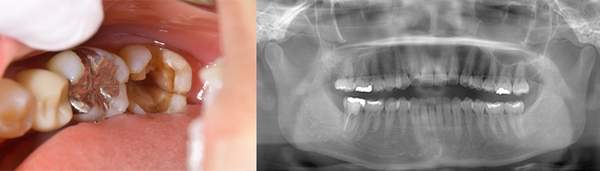

左のレントゲンでは破折したかどうかはわからないが、虫歯になっている部分をとっていくと歯が割れているのがはっきりとわかりました。

歯が割れるケースで多いのが金属の土台(メタルコア)が入っている場合です。特に根の中に長いものが入っていると、歯を割る力が強くかかるため、割れることが多いです。

ブリッジが取れたということでご来院患者様でした。レントゲンを撮ると縦に割れていました。

歯を抜くと、やはり割れていました。

歯の破折で抜歯したものです。

断面をみてみえると黒くなっているのがわかります。これは全部細菌です。歯がわれてしまうと、隙間に細菌が住み付き、繁殖してしまいます。そのため、骨や歯茎の中で炎症を起こしてしまいます。破折に気づかず根の治療をしても効果が得られないのです。

こちらは、歯の根の治療を行い、根の先端までキレイにし、防腐剤をしっかり詰めなおしましたが、膿が溜まったまま治癒しませんでした。破折に気づけなかったのです。

破折に気づいてからは、抜歯を行い、インプラントを入れてまた噛める様にしていきました。レントゲンでも破折がわからない時があります。そんな時はCTやマイクロスコープを使うとわかることが多いのです。